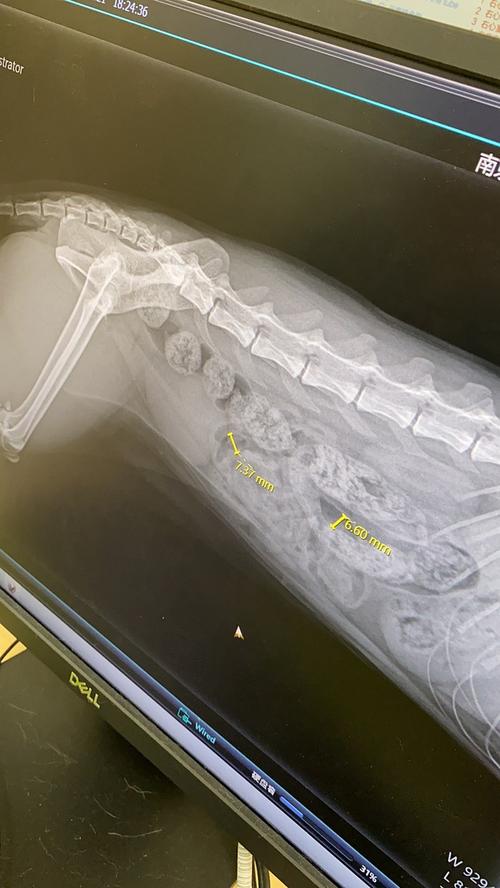

猫咪的普通体检,只需要挂号费即可,一般都是100元内。如果要抽血化验则在500内,拍x光和b超基本在150一项。猫咪身体检查费用为血常规检查五分类:80元全身临床检查:40元腹腔B超:元X光两张:240元内分泌:900元体检根据您的需求加项目,那就要看具体都是什么项目了!现在猫咪进个医院消费不低的。

〖肆〗、猫咪的普通体检,只需要挂号费即可,一般都是100元内。如果要抽血化验则在500内,拍x光和b超基本在150一项。猫咪身体检查费用为血常规检查五分类:80元全身临床检查:40元腹腔B超:元X光两张:240元内分泌:900元体检根据您的需求加项目,那就要看具体都是什么项目了!现在猫咪进个医院消费不低的。